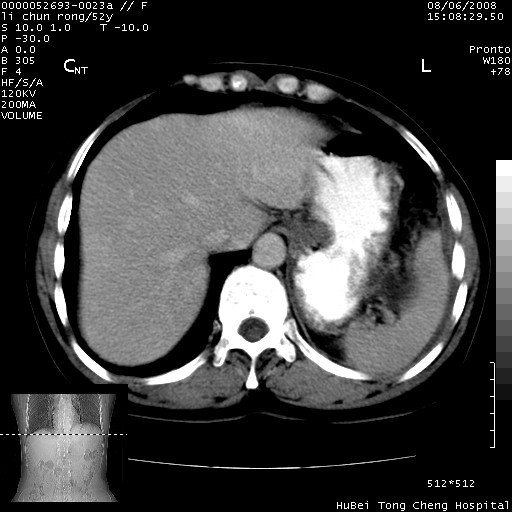

以下是引用云翔在2008-8-7 6:20:00的发言:[br]胰尾部囊性病变,考虑假囊肿,结合实验室检查疾病史

以下是引用zjzjr在2008-8-7 8:38:00的发言:[br]支持胰腺炎伴假囊肿形成,左肾小囊肿.少量腹水.

以下是引用随光逐影在2008-8-7 9:12:00的发言:[br]1)考虑胰腺炎伴假性囊肿形成可能性大;胰腺囊腺瘤待排。2)左肾小囊肿。3)少量腹水。